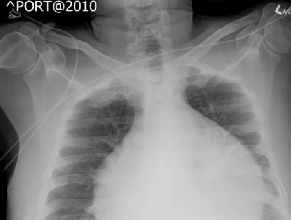

Chest X-rays

11/11/2013

Ronald N. Rubin, MD

A 62-year-old man presents with lower urinary tract symptoms. In the past year he has progressed from nocturia once nightly to 3-4 times currently.